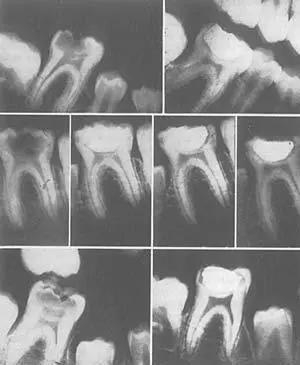

Рис. 97. Три случая иллюстрируют, как Природа может защитить пульпу, построив защитную стенку внутри углубления пульпы, после улучшения питания.

Питание детей, чьи зубы показаны на рис 97 было крайне скудным. Этих детей привели в наш центр, где мы давали им усиленное питание раз в день в полдень, шесть дней в неделю. Домашняя еда не менялась, также не менялся уход за зубами. Предварительный осмотр детей заключался в снимке всех зубов, химическом анализе слюны, тщательном изучении расположения, размера и глубины всех дыр в зубах. Также были записаны рост и вес детей, данные по оценкам в школе, включая оценки за поведение.

Эти данные замерялись каждые четыре-шесть недель на протяжении от трех до пяти месяцев. Важно отметить, что домашняя пища, которая вызвала разрушение зубов, была крайне бедна по содержанию витаминов и минералов и могла только временно утолять чувство голода. Обычно домашнее питание состояло из крепкого сладкого кофе с белым хлебом, растительных жиров, оладьев из белой муки с сиропом и пончиков, жареных на растительном масле.

То питание, которое давали детям мы раз в день, состояло из следующих продуктов: примерно четыре унции томатного или апельсинового сока и чайная ложка смеси из масла печени трески и сливочного масла, с высоким содержанием витаминов до начала еды. Далее им давали тарелку с овощами и тушеным мясом, включая костный мозг и вырезку: мясо обычно жарили отдельно, чтобы сохранить его сок, затем мелко резали и добавляли в мясной суп из костного мозга, который также содержал много резаных овощей и ярко-желтую морковь. Следующим блюдом они получали запеченные фрукты с очень маленьким количеством сахара и ролы из цельнозерновой муки свежего помола, намазанные маслом с высоким содержанием витаминов. Мука для этих ролов специально мололась каждый день на электрической кофемолке.

Каждый ребенок получал дополнительно два стакана цельного молока. Меню обновлялось ежедневно, чередуя тушеное мясо, рыбную похлебку и субпродукты. Проведенные анализы показывали, что каждый прием пищи обеспечивал детям примерно 1,48 гр кальция, 1,28 гр фосфора. Учитывая, что дети часто съедали две порции, потребление этих витаминов было гораздо выше. В предыдущей главе я указывал, что приемлемый уровень потребляемых витаминов составляет 0,68 гр кальция и 1,32 гр фосфора. Становится ясно, что одно усиленное питание плюс два другие приема пищи дома обеспечивают реальную защиту организму. Клинически подтвердилось, что такая программа полностью позволяла контролировать зубной кариес каждому члену группы.

Химический анализ слюны показал значительное улучшение. В начале теста среднее значение по группе давало крайне низкий уровень безопасности, и мы даже ожидали продолжения активного разрушения зубов. Через шесть недель средний показатель достиг уровня, при котором разрушение зубов должно останавливаться. Фактор безопасности слюны продолжал улучшаться на протяжении пяти месяцев, когда программа была окончена с наступлением лета.